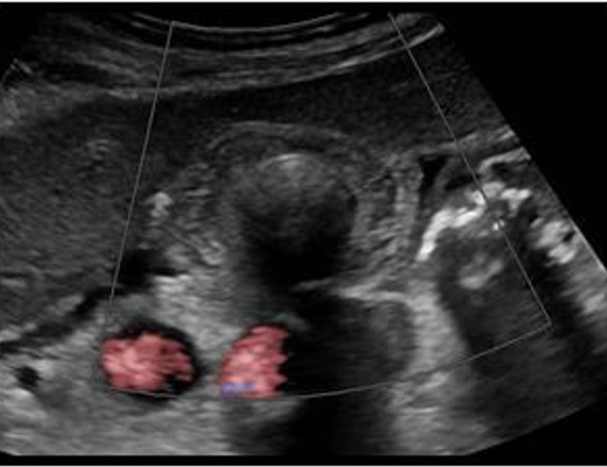

The image demostrate a critical finding of an aortic dissection. Note the aorta is separated into two channels by a flap of tissue. Aortic dissection is a common complication of Marfan syndrome